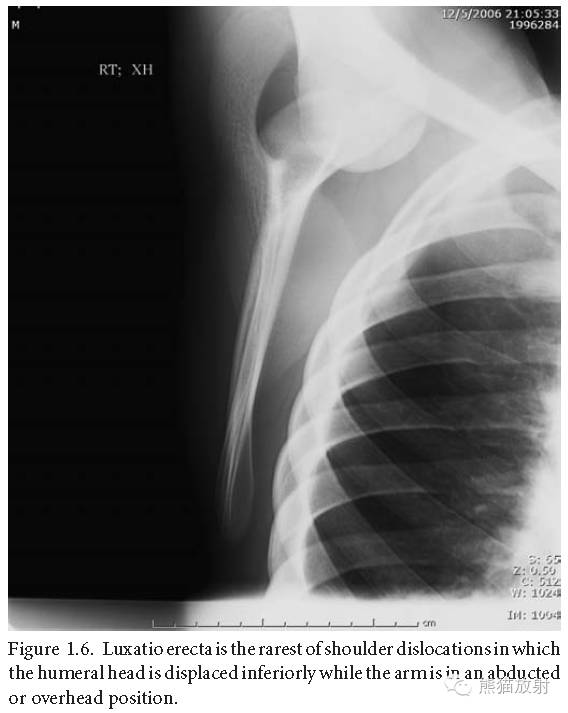

直举性肱骨脱位:罕见的肩关节脱位,肱骨头向下异位,而胳膊上举。